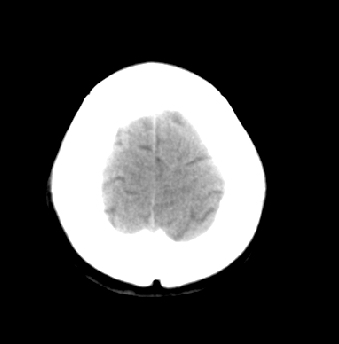

女性 38岁 病人脚弓反张 8岁以后不能行走 今年查pth11.9ng/ml(正常28ng/ml)

这么弥漫的钙化还第一次见。

考虑甲状旁腺功能减退症,该病是因甲状旁腺激素分泌减少或功能障碍所引起的少见病。其特点是低血钙,高血磷,且血pth极低。因低钙常可引起神经精神激惹症状,包括手指,趾,口角麻木,严重时可出现肌肉痉挛,喉哮鸣和惊厥,甚至癫痫样发作,有的可出现抑郁症及精神失常。长期的高磷血症可引起脑内结构对称性多发性钙化,特别是小脑和基底节的钙化可致锥体外系症状,而钙化的ct表现为类似于脑出血的密度增高影。

原发性甲状旁腺功能减退症和fahr病都有神志上的改变等症状,且头颅ct检查均可见颅内出现钙化。但fahr病无pth低下,ct表现钙化影在大脑半卵圆中心皮髓质交界处、丘脑、小脑齿状核等处。 而甲状旁腺功能减退症pth极低,ct虽可见钙化影,但部位在小脑和基底节等处。